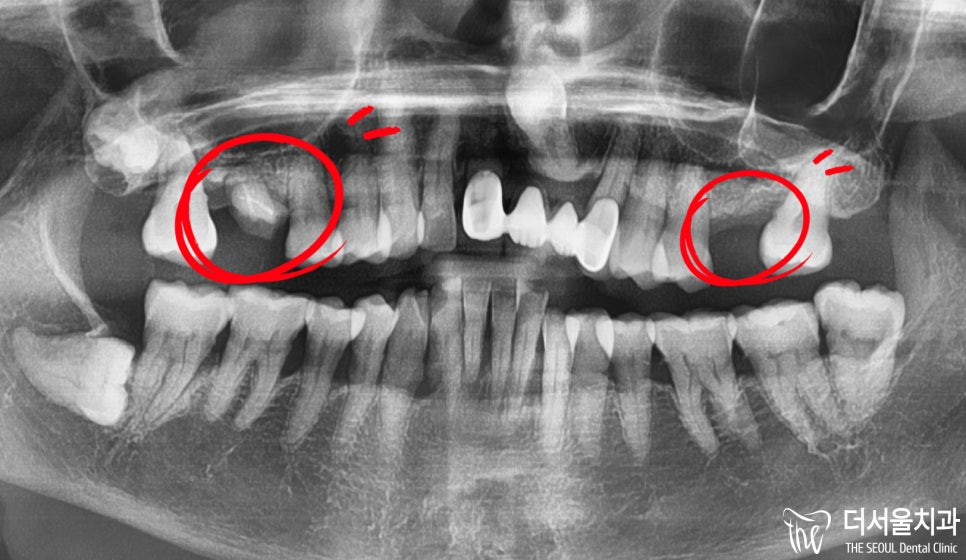

반갑습니다. 판교역 더서울 치과 쌍둥이 박현성 원장입니다. 오늘 보여드릴 임플란트 케이스는 조금 특이했다고 말씀드릴 수 있는데요. 환자분께서는 초등학교를